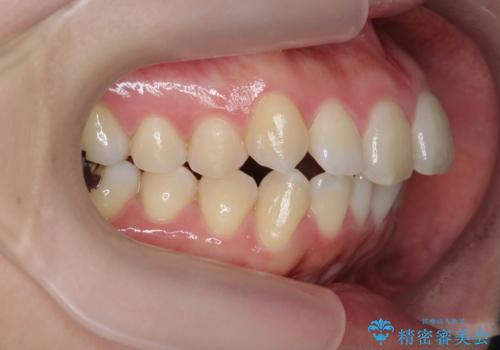

咬合関係の改善、前歯の角度、がたつきを改善するため、マイクロインプラントを用いて上顎の奥歯を後方へ移動させていきます。

矯正治療後、前歯のがたつき、咬合関係が改善され満足いただくことができました。